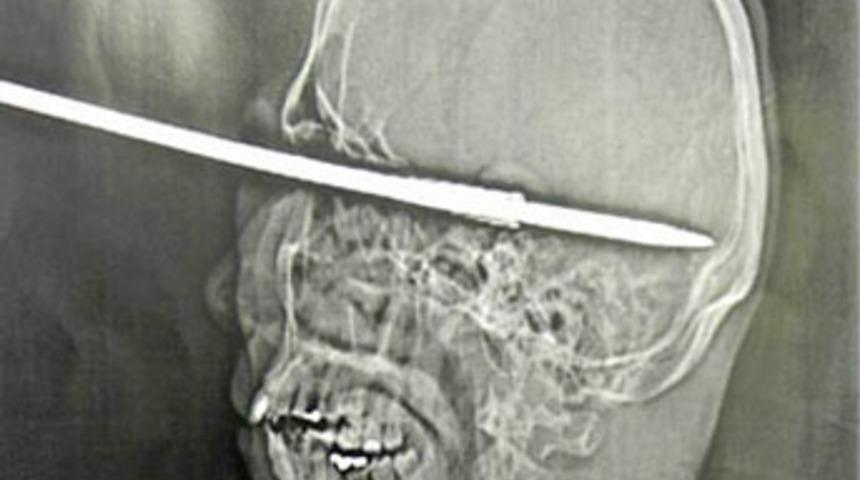

RIO DE JANERIO (İHA) - Zıpkını temizlemesi sırasında yanlışlıkla ateş etmesi sonucu sol gözünden kafasına 15 santimetre uzunluğunda zıpkın saplanan Coutinho, olay sonrası bilincini kaybetmeden halasına bağırmayı başardı. Hemen hastaneye kaldırılan Coutinho, tedavi altına alındı. Doktorlar Coutinho’nun gözünden 10 saatlik operasyon sonrası zıpkın çıkarmayı başardı. Coutinho’nun beyninde bir hasar oluşmadığını ifade eden doktorlar, şanslı adamın sol gözünü fiziki olarak kurtardıklarını fakat görme yetisini kaybettiğini açıkladılar.